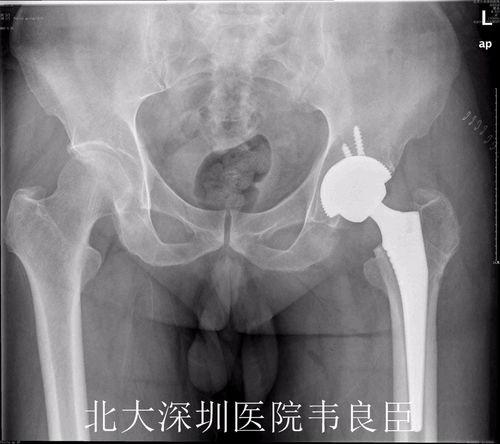

在手术之前,医生会为你进行一系列的检查,以确保手术的顺利进行。这些检查包括但不限于X光、CT扫描和血液检查。通过这些检查,医生可以了解你的髋关节状况,评估手术的可行性。

置换股骨头手术通常分为两个部分:股骨头置换和髋臼置换。下面,我们就来详细了解一下手术过程。

首先,医生会在患者的髋关节处切开一个小口,然后取出坏死的股骨头。接着,医生会植入一个新的股骨头,这个股骨头通常由金属制成,具有良好的生物相容性。

视频中,我们可以看到医生正在小心翼翼地取出坏死的股骨头,并植入新的股骨头。手术过程中,医生需要确保新股骨头与髋臼紧密贴合,以恢复髋关节的正常功能。

在完成股骨头置换后,医生会继续进行髋臼置换。首先,医生会在髋臼处切开一个小口,然后取出坏死的髋臼部分。接着,医生会植入一个新的髋臼,这个髋臼通常由陶瓷或金属制成。

视频中,我们可以看到医生正在为患者植入新的髋臼。手术过程中,医生需要确保新髋臼与股骨头紧密贴合,以恢复髋关节的正常功能。